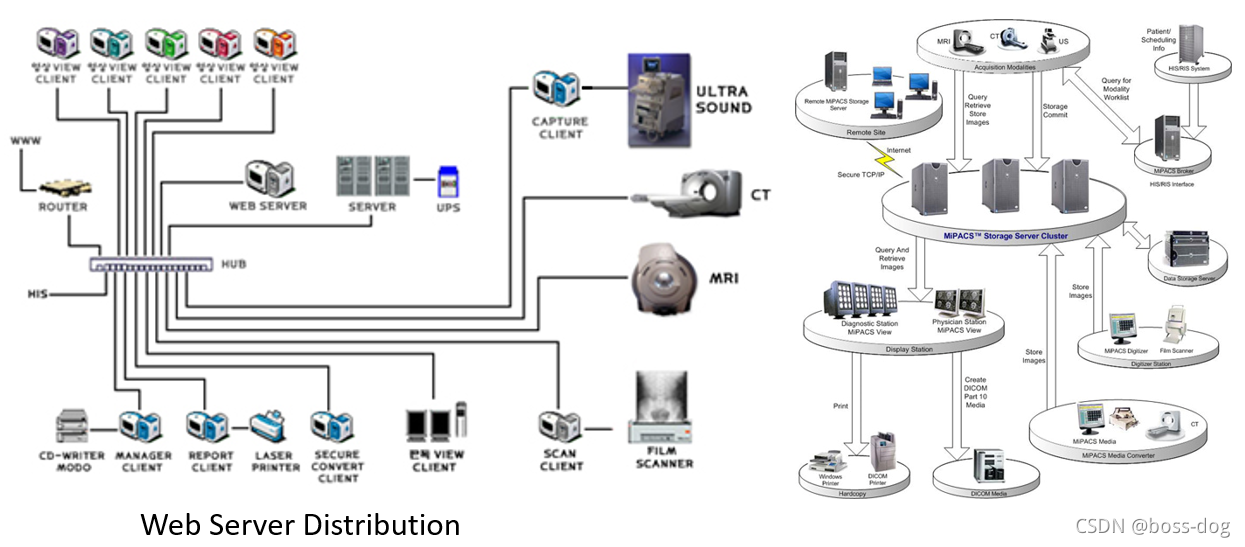

7.PACS

7.1 PACS介绍

-

PACA定义:用于必要时存储和分发图像信息的系统。

P:图片、图像和报告

A:存档、在线、近线、离线

C:通讯、网络、传输协议

S:系统、组成、架构 -

PACS: Small or Large

7.2 PACS架构

PACS分为两种:一种是图像的服务器为中心(PACS – Central Architecture),还有一种是分布式的(PACS – Distributed Architecture)。

PACS – Central Architecture的优缺点:

优点:传输起来的统一管理,并且所有的数据都在服务器里面方便管理。

缺点:服务器的功能需要非常强大,以满足不停的接收和分发那些图片和信息,需要很高的性能;而且如果服务器坏了,导致整个系统瘫痪;对带宽也有一定的要求。

PACS – Distributed Architecture的优缺点:

优点:比如MR扫描出来的图像就直接到了临床医生或者放射科医生的面前,就不需要第三方的服务器;如果服务器坏了,也不影响整个系统。

缺点:需要复杂的路由算法;如果大家都需要同时看一些图,那么分布式的结构就由一定的困难。

- PACS系统的组成:

HIS/ RIS(关于病人的信息、预约信息)

Broker(代理)

ePR gateway(网关)

Database Server(数据库)

Image Server (RAID)(图像数据库)

Long Term/ Near line Archive(长期、近期的档案整理)

Networks(网络)

Digitizer(数字化处理)

Acquisition Gateways(采集网关)

Non-DICOM modality gateway(非DICOM格式图像的处理)

DICOM Print Server(需要连接胶片打印机)

Media Server(拷刻成光盘)

Reporting Server(形成意见报告)

Monitor QC Server(和显示器的连接)

Web Server(Web服务端)

Workstations(给医生看图片的工作站)